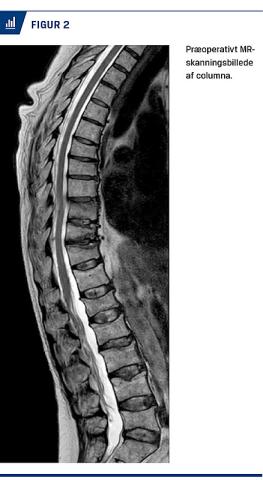

Man bør være opmærksom på kompressionsfrakturer ved spontant opståede rygsmerter eller ved rygsmerter, der er opstået ved beskedne traumer. Diagnosen bekræftes med konventionel røntgenoptagelse af columna i to plan. Hvis man påtænker at tilbyde patienten PVP, er der behov for en MR-skanning (Figur 2). Hos patienter med osteoporose indikerer aktivitet på en MR-skanning med STIR-frekvens et friskt sammenfald/manglende heling af frakturen [15]. Dette har betydning for, om man kan tilbyde PVP, da behandlingen ikke har vist effekt på sammenfald uden aktivitet [15]. Ved mistanke om maligne læsioner kan man ofte bekræfte diagnosen og visualisere en læsion af hvirvlens bagkant ved skanning. En sådan læsion er en relativ kontraindikation for PVP pga. risiko for cementlækage ind i spinalkanalen [16]. Ved sammenfald, der er opstået pga. myelomatose, ses der ikke altid aktivitet på en MR-skanning [17]. Tilbud om PVP til patienter med myelomatose afhænger af den kliniske vurdering [18].